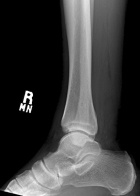

50 year old male with a several year history of right ankle mass, which the patient states has gotten larger in the past few months. On PE he has a tender, egg shaped mass in the distal posterior aspect of his left calf.

Zoom image: Radiological image Radiological image.